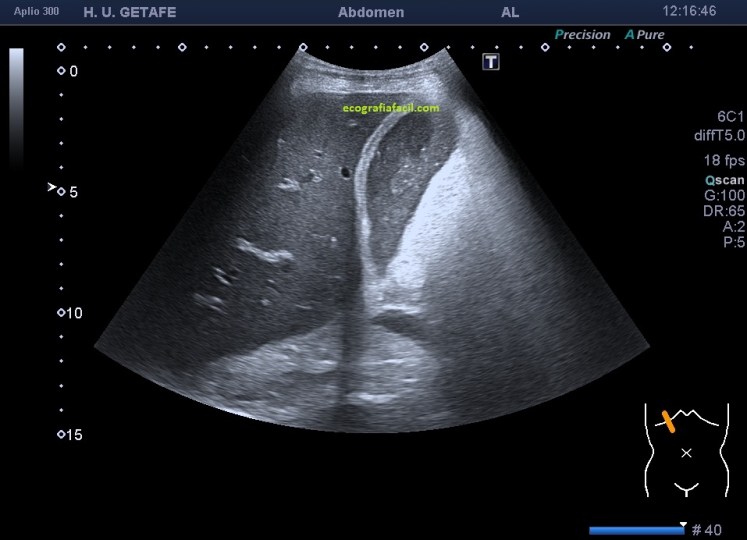

Podemos encontrarnos niveles hidro-hidro, donde podemos ver, el contenido biliar normal, anecoico como en la imagen 1, con barro, cuya ecogenicidad correspondería con la imagen 2 y tendrías la imagen 3.

Finalmente, la imagen 4, donde encontramos una vesícula sin barro biliar y con una gran colelitiasis que provoca una evidente sombra acústica posterior. La vesícula es anecoica, sin presencia de barro, el paciente puede ser completamente asintomático y no saber que esa ecoestructura, redondeada, hiperecogénica causante de sombra acústica posterior y móvil, que así suelen ser las colelitiasis, se alberga en el interior de su vesícula. Las colelitiasis suelen ser variable en número, tamaño e incluso forma.